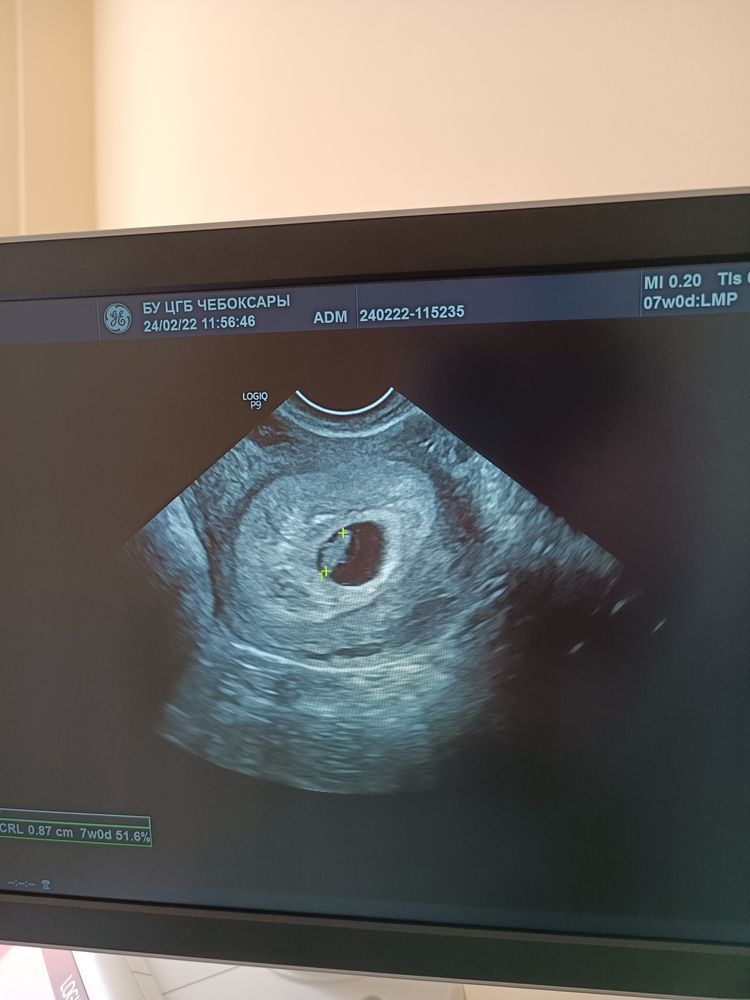

Но шло всё на удивление неплохо (только живот болел постоянно как перед месячными), поэтому 24-го февраля я впервые увидела свою малявку на экране монитора и услышала стук ее сердце. В тот день также обнаружилась угроза из-за тонуса и небольшой гематомы.